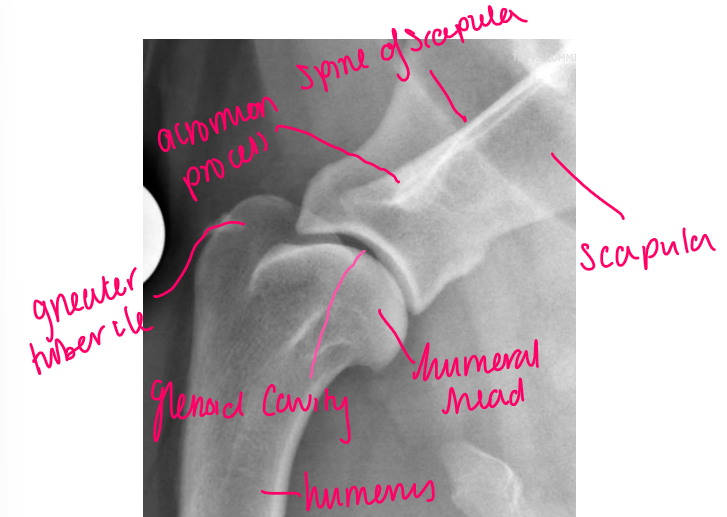

What should be seen in a well positioned lateral view radiograph of the shoulder?

In a well positioned radiograph the joint space should be well visualised and there should be no overlying tissue

Some radiographers deliberately try to overlie the shoulder joint with the trachea to increase contrast

label

acromion process

spine of scapula

scapula

humeral head

humerus

glenoid cavity

greater tubercle